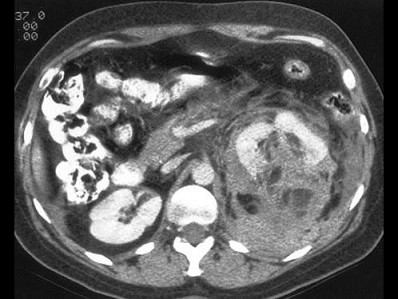

A.左肾癌

B.左肾脂肪瘤

C.左肾脂肪肉瘤

D.左肾脓肿

E.左肾血管平滑肌脂肪瘤